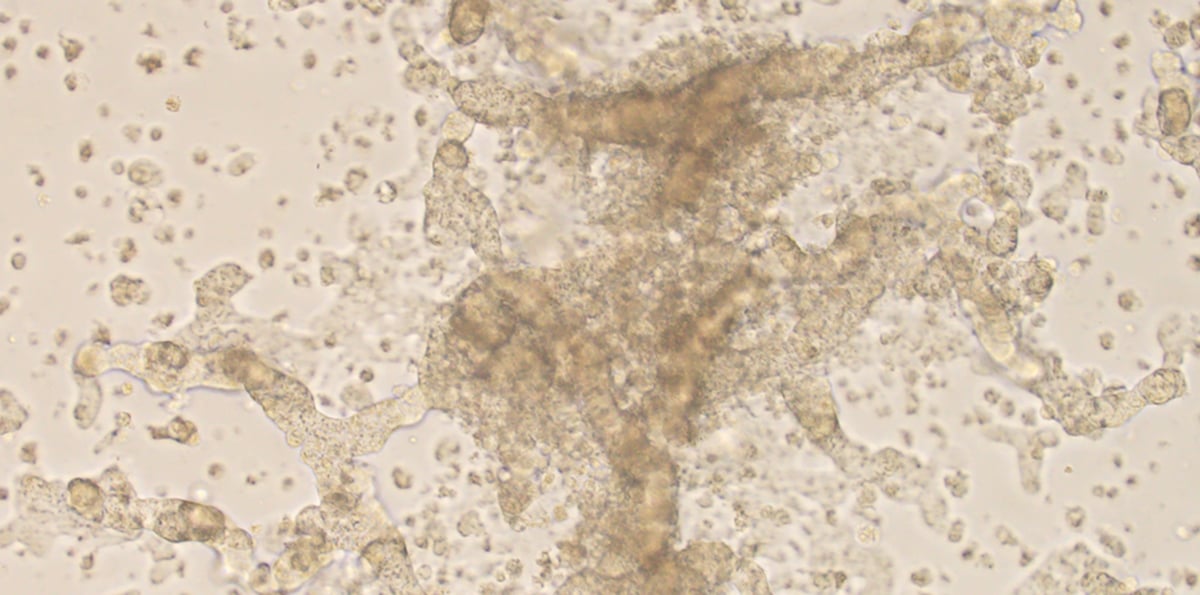

living cancer cells

This is a photo of Emily Daniels' living cancer cells studied in Dr. Robert Doebele's lab on the CU Anschutz Medical Campus.

“Entirely because Dr. Doebele was able to grow the cells in a lab, we were able to say for the first time to a patient, ‘Look, your cancer cells have tons of MET signaling going on,’” Camidge said. “In the living cell lines, if we put on a MET inhibitor as well as an ALK inhibitor, they get really unhappy.

“Emily is technically the only patient I know of that has this exact mechanism resistance,” he said.